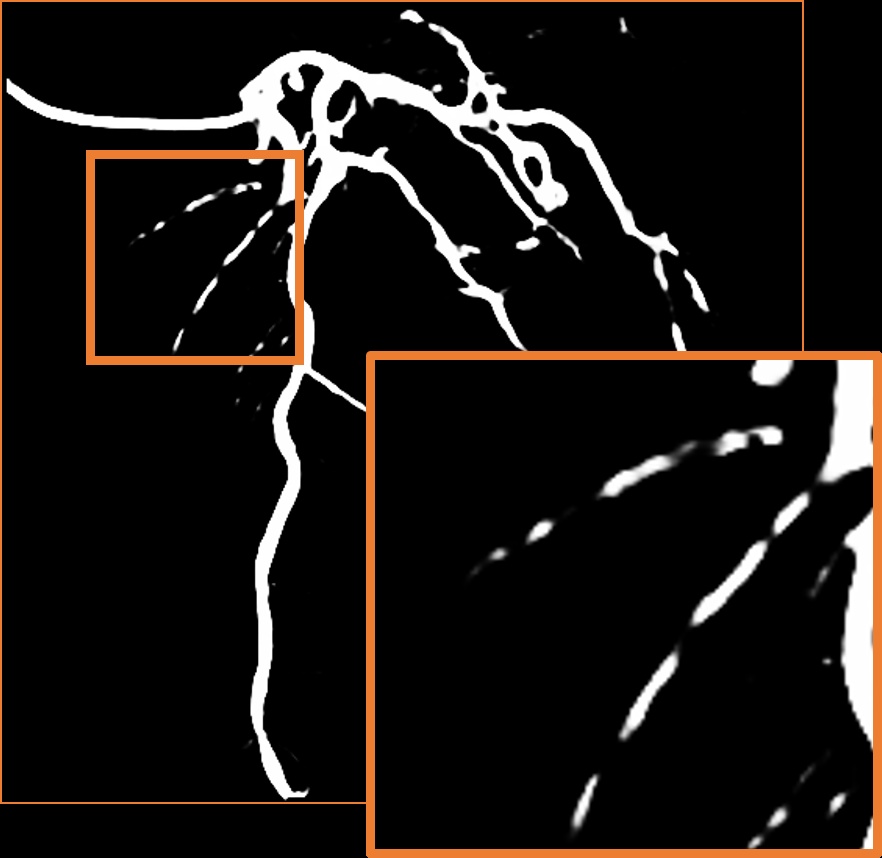

Parallel vessel motion loss .

We conduct an experiment to assess the effect of the parallel vessel motion loss by removing it from the training pipeline. As shown in Table 2, the segmentation performance decreases the Dice score by 0.0047. Without this loss to enforce parallelism between blood and vessels, the segmentation results are negatively affected. In addition, the comparison between without and with is shown in Figure 8 (c). The zoom-in patch shows that the image with has clearer segmented vascular regions.